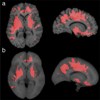

Results: Severe atrophy ( approximately 15-20% deficit) was detected bilaterally in the primary and association sensorimotor areas. Atrophy of these regions, particularly in the white matter, correlated with cognitive impairment (P = 0.033) and CD4+ T-lymphocyte depletion (P = 0.005).

Conclusion: TBM facilitates 3D visualization of AIDS neuropathology in living patients scanned with MRI. Severe atrophy in frontoparietal and striatal areas may underlie early cognitive dysfunction in AIDS patients, and may signal the imminent onset of AIDS dementia complex.